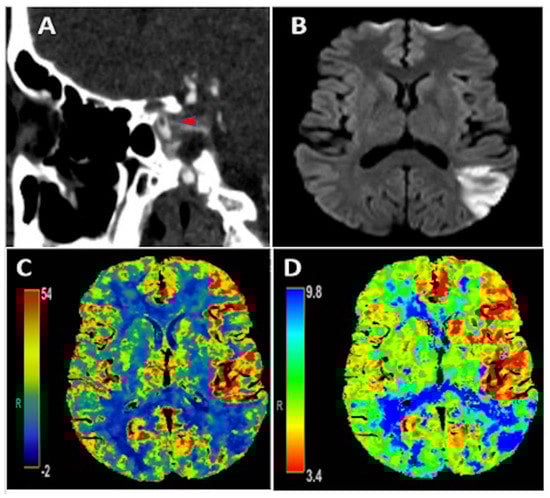

An early 50-year-old male with type 2 diabetes mellitus and hyperlipidemia presented with isolated transcortical sensory aphasia that correlated with a National Institute of Health Stroke Scale (NIHSS) of 3. CT angiography showed a free-floating intraluminal thrombus in the clinoid segment of the left internal carotid artery (Figure 1A). There was subtle hypervascularity of the anterior left middle cerebral artery (MCA) territory with an increase in regional cerebral blood flow (CBF) (Figure 1C) and cerebral blood volume (CBV), as well as decreased Tmax (Figure 1D) on perfusion imaging, consistent with hyperperfusion. Additionally, there was an area of decreased CBF and increased Tmax in the posterior left MCA territory, consistent with core infarction, which correlated to ischemic infarct area seen on MRI brain diffusion weighted imaging (Figure 1B). He did not receive acute reperfusion therapy due to presentation beyond the therapeutic window, as well as absence of favorable perfusion characteristics on initial imaging. Additionally, he was found to have an acute inferior-wall ST-elevation MI with initial troponin of 4.97 ng/mL that peaked at 10.79 ng/mL. Cardiac catheterization was deferred given the risk of hemorrhagic transformation of AIS with high doses of anticoagulation and dual anti-platelet therapy that would be needed. No contributive cardiac pathology was found on transthoracic echocardiography, cardiac CT with contrast, or on telemetry that was continued throughout admission. As an outpatient post hospital discharge, the patient had Holter monitoring that recorded about 117 hours of data and did not show any evidence of atrial fibrillation. Hypercoagulable work-up was completed both as an inpatient and also one month after hospital discharge and was unrevealing. The patient reported a recent COVID-19 exposure and clinical symptoms of chills in the days preceding this presentation, with pulmonary imaging showing peripheral ground-glass opacities in a pattern consistent with COVID-19 pneumonia. Swab-based PCR testing for COVID-19 was negative, but the IgG antibody test returned positive, suggesting recent infection. D-dimer was elevated at 1218 ng/mL on admission. He was initially treated with therapeutic anticoagulation with intravenous (IV) heparin; however this was discontinued 36 hours later due to petechial hemorrhage, as seen on repeat head imaging. He was subsequently treated with antiplatelet monotherapy. Magnetic resonance imaging (MRI) of the brain confirmed an AIS involving the left MCA territory (Figure 1B). He had an uncomplicated hospital course and was discharged in good condition with NIHSS of 2 for a mild aphasia. CT angiography of the neck was repeated one month after hospital discharge and showed resolution of ILT.

Figure 1.

Panel (A): CT angiography showing an intraluminal free-floating thrombus (red arrowhead) in the clinoid portion of the left internal carotid artery; Panel (B): MRI brain diffusion weighted imaging illustrating an acute ischemic stroke in the posterior left middle cerebral artery (MCA) territory. Panels (C,D): CT perfusion depicting increased CBF and decreased Tmax, respectively, in the anterior left MCA territory consistent with hyperperfusion in this area as well as decreased CBF and increased Tmax in the posterior left MCA territory consistent with core infarction and corresponding with ischemic stroke seen on MRI brain in Panel (B).